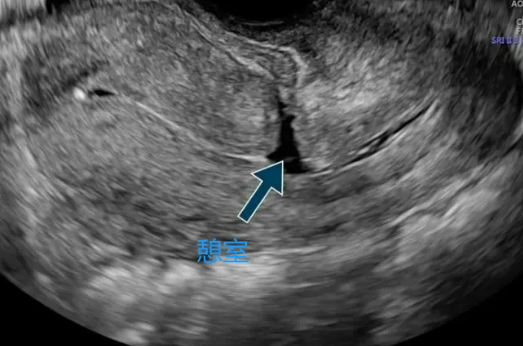

▲B超下瘢痕憩室

去年9月,怀揣着三孩梦的周女士夫妻二人来到深圳恒生医院生殖医学科,敲开了邓伟芬主任诊室的门。邓伟芬主任经过一番的细致问诊,初步判断周女士五年备孕无果的原因主要是子宫切口憩室(即瘢痕憩室,指剖宫产术后子宫切口愈合不良,子宫瘢痕处肌层变薄,形成一与宫腔相通的凹陷或腔隙,患者多无明显的临床症状,有症状者仅约6.9%,主要表现为异常阴道流血、继发性不孕、慢性盆腔痛、经期腹痛等)、反复宫腔积液、子宫内膜炎,使得胚胎难以在宫腔内着床受孕。